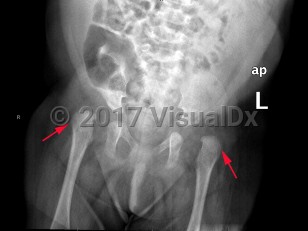

Developmental dysplasia of the hip in Child

A spectrum of developmental abnormalities of hip joint dislocation or subluxation of the acetabulum and proximal femur (head), typically diagnosed in infants and children. Most often unilateral, but may be bilateral (20%). Common signs and symptoms include hip instability, pain, limited range of motion, abnormal gait, and limping. It may be associated with breech birth, family history, or social practice of swaddling. Some neuromuscular disorders may be associated with hip dysplasia. Early intervention decreases lasting and progressive damage, limiting functional disability and preventing early-onset osteoarthritis. Many cases of infant hip instability will gradually stabilize.